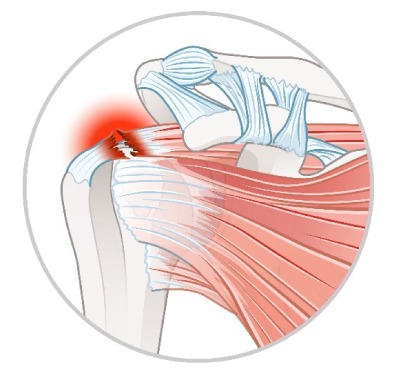

関節鏡下肩腱板断裂手術

画像引用:伊藤整形・内科 あいちスポーツ・人工関節クリニック

Journal of Shoulder and Elbow Surgery

関節鏡下肩腱板断裂手術とは

肩のインナーマッスルに障害があり、腱が断裂する状態を腱板断裂と呼びます。四十肩・五十肩とは異なり、断裂の大きさによっては手術が必要となる場合があります。

関節鏡下肩腱板断裂手術は、主に棘上筋・棘下筋の断裂を修復するために行われます。関節鏡を用いて、5~6か所の小さな穴(ポート)を通して特殊な糸を使い、機械で筋肉を縫合・修復します。

手術は全身麻酔で行われ、所要時間は約2時間です。術後の退院は1週間程度が一般的です。